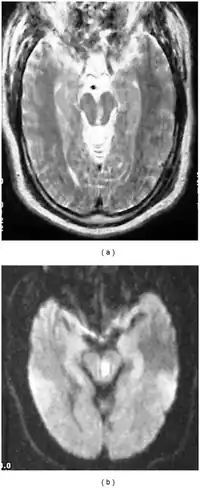

| a,b) Severely motion degraded axial T2-weighted and DWI images of midbrain demonstrate a subacute infarct within the left midbrain tegmentum | |